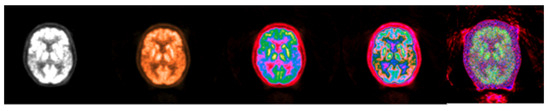

3.1. CIT Application

3.2. Colormap Folding Application